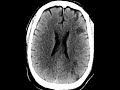

Watershed Infarcts

This patient had a history of PEA (pulseless electrical activity) arrest and acute right-sided neurological deficits. The CT shows multifocal areas of wedge-shaped hypoattenuation involving the cortex and subcortical white matter of the left frontal and parietal lobes at the expected junction of the major arterial territories. In addition, there is hypoattenuation of the left centrum semiovale at the expected border of the perforating arteries. Findings are compatible with watershed or hypotensive infarctions which fits clinically with this patient’s history of cardiac arrest. Given the unilaterality of the findings, the patient may have a stenosis of the left carotid predisposing the left cerebral hemisphere to the ischemic insult following the drop in blood pressure. Differential considerations include embolic infarcts.